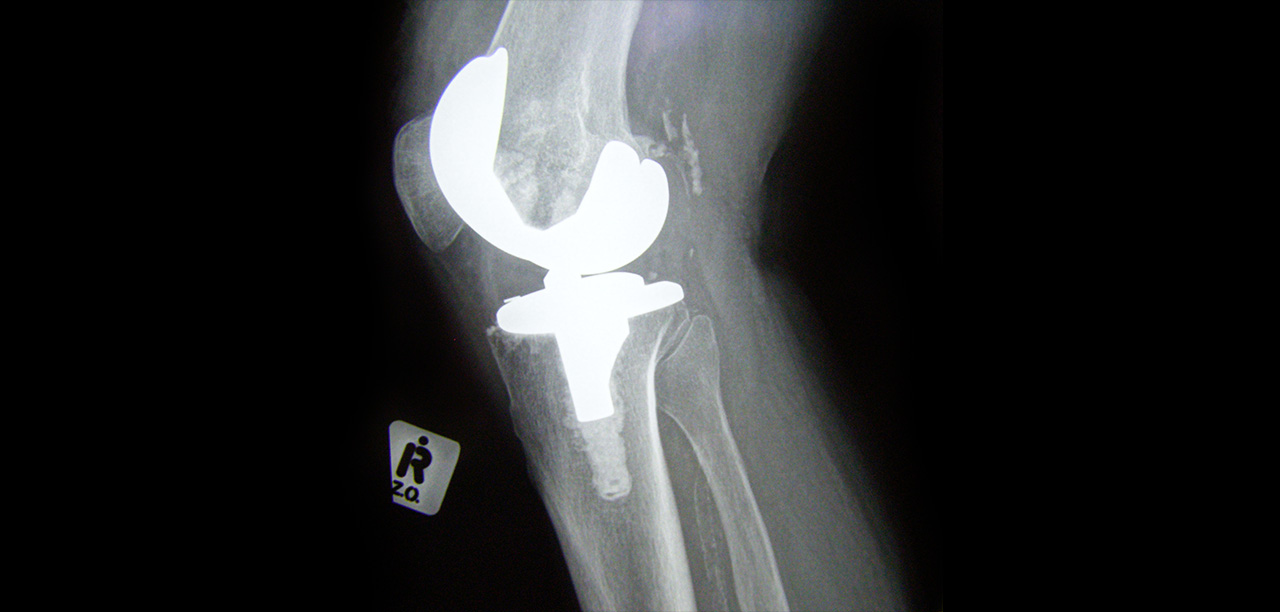

Total Joint Replacement in Medicare Beneficiaries from 2009 to 2017: Disparities and Geographic Variation

Posted By: Thomas Einhorn, MDThere are insufficient data on the geographic variation and disparities in the use of elective primary total hip and knee arthroplasty for Medicare beneficiaries.